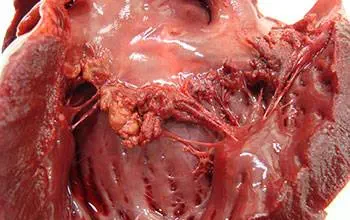

سه نوع از عفونت قلب وجود دارد:

پریکاردیت (Pericarditis)، که روی بافت اطراف قلب اثر می...

کاردیومیوپاتی (cardiomyopathy) عبارت است از: ضخیم شدن و سفت شدن عضله (ماهیچه) قلب. مراحل ا...